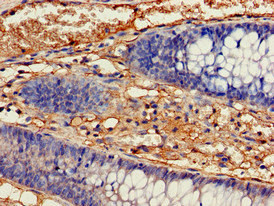

Immunohistochemistry of paraffin-embedded human colon cancer using CSB-PA010989EA01HU at dilution of 1:100